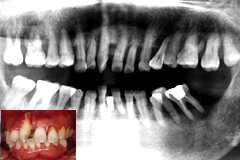

| 術前(初診時) パノラマ | 術後(治療終了時) パノラマ |

| 歯周疾患末期 47歳 女性 |

上顎は手術不能 |

初診時口腔内およびX線所見:

清掃状態、歯槽骨の残存状況ともに不良。

特に上顎前歯部の骨植は悪く、手術をすれば必ず数本が脱落しそうな状況であった。

処置および経過:

上顎は、歯肉を剥離しての手術は不可能と判断し、根管治療およびルートプレーニングバー

による根面処理を行ったのち残存可能な歯を全て連結固定。

下顎は、Fop + Nd:YAG LASER による根面処理を行ったのち連結固定してメインテナンスに移行。

術後5年を経過した現在、歯肉が再び腫脹傾向を示すものの機能上は問題なし。

考察:

根面処理と連結固定。間違いなく歯の寿命を延ばす治療だと思います。でも、患者さんの

強い意思と協力がなければ長期保存の価値は失われてしまいます。治療の良し悪しは、

治療するドクターと患者さんが決めるものだと思います。

感想:

「上顎は最善は尽くすけどあきらめてね。その代わり、下顎だけでも入れ歯にならないよう

頑張ろうね。」と言って始めた治療です。それでも、上顎は5年、下顎は10年以上もつだろうな

と思っていました。5年経過した現在、初期の約束は果たせたものの、さぁ何時までもつのやら?

| 術前(初診時) パノラマ | 術後(術後5年) パノラマ |